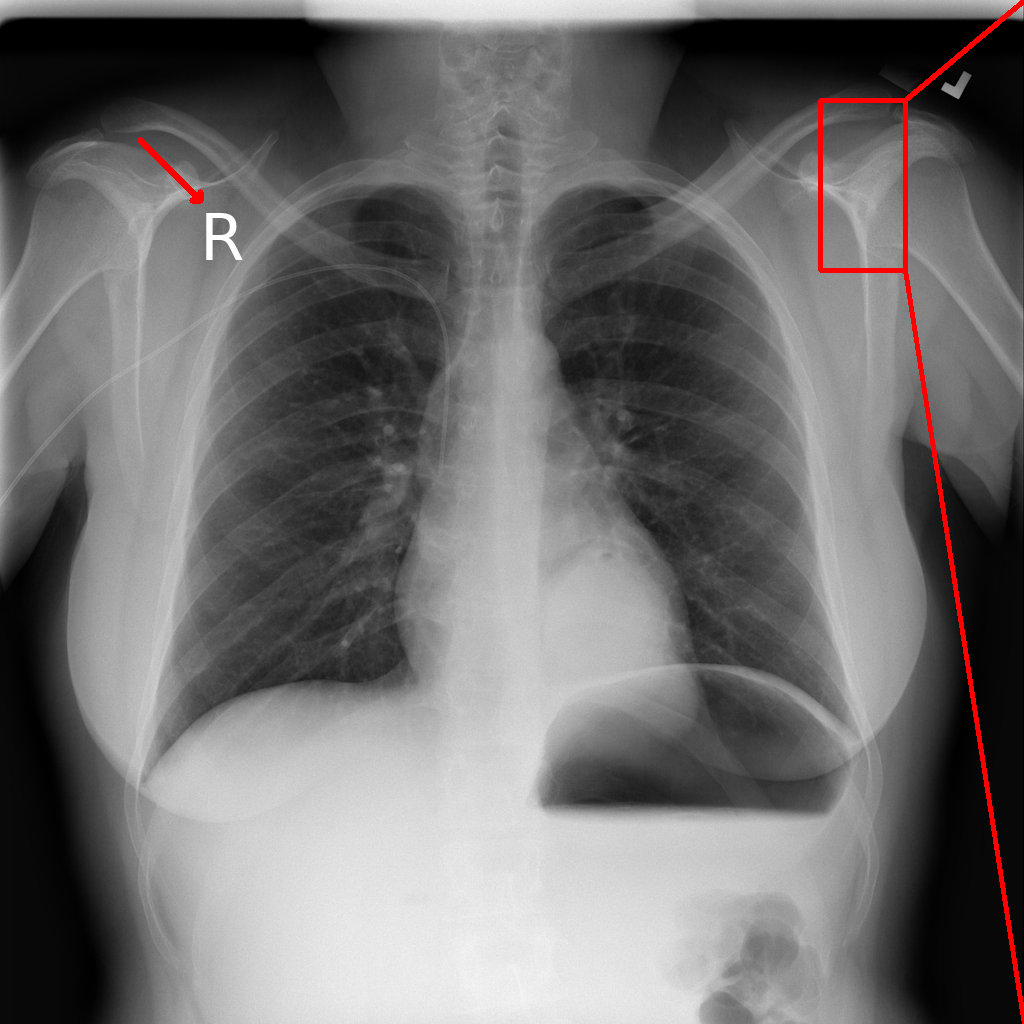

• An external confounder (a tag) placed in the upper left corner of the image, representing confounding features introduced by various imaging devices across or within hospitals (Fig. 5(a)).

Figure 2: Synthetic artifacts: (a) A tag with a red arrow for reference, (b) a zoomed-in view of the original image, (c) Denoising by low-pass filter with cutoff frequency (see Eq. 1) of D0=200subscript𝐷0200D_{0}=200px, and (d) Poisson noise with N0=2×106subscript𝑁02superscript106N_{0}=2\times 10^{6} (see Eq. 2). The parameters used here are to emphasize subtle local variations such as the smoothing effect of the low-pass filter and the graininess introduced by the Poisson noise. For our experiments, we use D0=500subscript𝐷0500D_{0}=500px and N0=2×107subscript𝑁02superscript107N_{0}=2\times 10^{7} which are imperceptible.

Confounder generation. A tag is placed further away from the edges (starting at 200×200200200200\times 200px in the original image of 1024×1024102410241024\times 1024px), to ensure it remains intact during training despite augmentations applied (Fig. 5(a)).